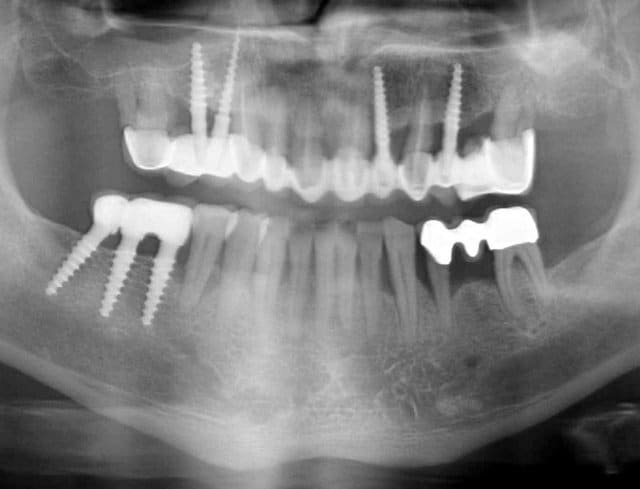

Pour ceux que ca interessent, et parce qu on a m a demandé des cas supplémentaires dans le sujet 23 implants rehabilitation totale, voici un autre cas d implantation immédiate avec la technique minimalement invasive et condensation grace aux forets.

Le patient a reçu un traitement il y a dix ans dans le maxillaire et dans le 4eme quadrant.Comme on peut le voir j´ai du extraire quelques dents au maxillaire: 35 37 et 45.

Le septum de la 37 a été foré avec un foret conique 3 faces.

J ai planté à 60 Ncm sans fracturer le septum.Juste après l opération , les prep caps en zircon ont été cémenté.La restauration définitive 34 jusqu` à 37 été fixé 2 semaines après l implantation avec implantlink (detax). Après un an, le bridge a été retiré facilement pour voir l´état de la gencive et faire une radio de contrôle.On la re ossifiction est satisfaisante et que la gencive "aime" le zircon.

Le bridge a ensuite été recémenté sans correction nécessaire du bridge.